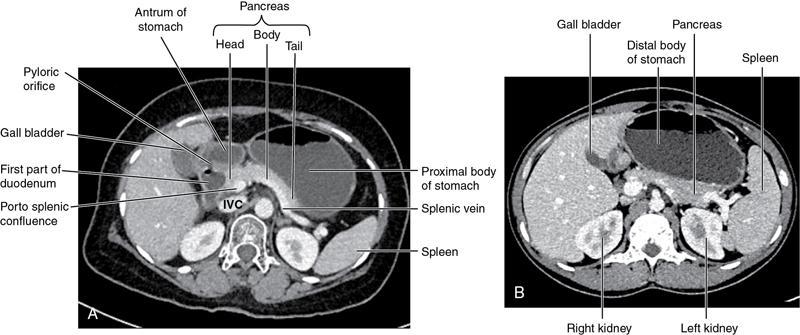

CROSS SECTIONAL ANATOMY OF ABDOMEN Satya Jha NORMAL ANATOMY OF ABDOMEN AND PELVIS Amandeep Singh The two major surfaces: The anterior and posterior layers of the coronary ligament converge on bare area (not covered by peritoneum). Its right and left margins form the right and left triangular ligaments. The right triangular ligament extends toward the diaphragm and separates right subphrenic space from right subhepatic space. The left triangular ligament gives tracts extending to the diaphragm and falciform ligament and does not compartmentalize the left subphrenic space. Ligamentum teres or the obliterated umblical vein is contained in falciform ligament which attaches the liver to anterior abdominal wall. The main portal vein, the proper hepatic artery and the common bile duct are contained within investing peritoneal folds of hepatoduodenal ligament at the porta hepatis (Fig. 7.2.2.1). Liver is divided into eight segments which are functionally independent and have their own vascular supply and biliary drainage. Arterial circulation: The branches of the hepatic artery accompanying the portal veins. Hepatic venous system: The right, middle, and left hepatic veins draining into IVC (Figs. 7.2.2.2 and 7.2.2.3). The gallbladder is a blind pear-shaped muscular membranous sac which is an embryologic derivative of the foregut, is a pouch lying along the undersurface of the liver. The gallbladder fossa is located in the plane of the interlobar fissure, which lies between the right and left hepatic lobes. Its major function is to store and concentrate bile which is produced by the liver. It measures approximately 4 cm in diameter when it is normally distended. Gallbladder is a smaller tubular structure in contracted state. The normal gallbladder wall thickness ranges from 1 to 3 mm. The gallbladder is divided into the fundus, body and neck. Infundibulum is present in the region of neck of the gallbladder, which is called the Hartmann pouch, where gallstones are usually impacted. Intrahepatic biliary radicles (IHBRs) scattered throughout the liver get confluent towards the hilum. They unite to form the right and left main hepatic ducts which further unite to form common hepatic duct (CHD) at the hilum. Common bile duct is formed by the union of cystic duct with common hepatic duct. The main pancreatic duct is joined with the common bile duct to form the ampulla of Vater at the major duodenal papilla (Figs. 7.2.2.4 and 7.2.2.5). Pancreas is located in anterior pararenal space of retroperitoneum anterior to perirenal (Gerota’s) fascia and posterior to parietal peritoneum. It is divided into head, uncinate process, neck, body and tail from right to left. Pancreas lies anterior to portal vein, which marks the point of transition between the body and neck. The region between head of pancreas and second and third parts of duodenum is known as the pancreatic groove. In postnephrectomy cases or with agenesis of kidney or ectopic kidney, pancreas moves posteriorly to partially fill in the empty renal fossa; its soft tissue density should not be mistaken for recurrent tumour. It is located in the pancreatic groove and is bounded superiorly by the duodenal bulb, laterally by second portion of duodenum, inferiorly by third portion of duodenum, medially by superior mesenteric vein and anterior to inferior vena cava. It is a wedge or wedge shaped lying posterior to superior mesenteric artery and vein. It is an imaginary junction between the head and body and lies directly over the junction of the splenic vein and superior mesenteric vein. It is located posterior to the lesser sac and anterior to the aorta, left adrenal gland, left kidney, and renal vessels and runs obliquely upward to the left of the superior mesenteric vessels. It is situated median to the colonic flexure and anterior to the left kidney. It is located in close proximity to the splenic hilum without a notable relation with the body of pancreas. It is seen anterior to the left kidney and median to the colonic flexure. The distal part of the tail passes between the peritoneal layers of the splenorenal ligament (Fig. 7.2.2.6 and 7.2.2.7).

Pancreas

Normal anatomy and relationships of pancreas

Head

Uncinate process

Neck

Body

Tail